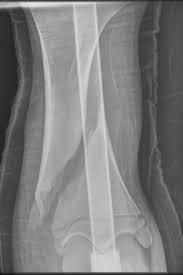

X線写真では骨折線が明らかに認められ、仮骨が非常に少なく、骨の断端は輪郭が不鮮明です。また偽関節では、患部に異常可動性があり、無痛で、X線写真でみると、骨の断端が丸くなっています。

骨髄腔の開口部が閉鎖されている、断端間に輪郭の明瞭な間隙がある、断端の骨の陰影は濃いが、そこから少し離れた部位の陰影は薄く、無機質が減少している、骨折部で骨が屈曲している、などの所見があり、再手術によらないかぎり治癒の可能性がない。

骨の断端部の血液循環が停止して、骨の再生反応がなく、X線写真では断端の骨組織の陰影が薄いか、認められません。断端の間隙は、結合織か軟骨で埋められています。

断端が丸味を帯びる、骨髄腔の端が蓋でふさがれている、などの点は象足型と同様ですが、外骨膜性の造骨反応がなく、新関節を形成しない。